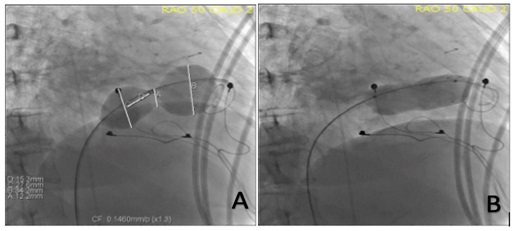

Subsequent work-up included an abdominal ultrasound that showed hepatic congestion and cirrhosis. A cardiac magnetic resonance imaging (MRI) showed tricuspid stenosis, likely due to dysplastic tricuspid valve leaflets that appeared thickened without significant TR. The tricuspid valve annulus measured 24 mm in transverse diameter and 23 x 32 mm in short axis. The tricuspid valve annulus area was 5.5 cm2. A transesophageal echocardiogram confirmed a narrow, hypoplastic, dysplastic, and lipomatous tricuspid annulus measuring 1.7 x 2.1 cm at the base of the tricuspid leaflets (Figure 1A). There appeared to be commissural fusion and restriction of the leaflet tips with a peak gradient of 18 mm Hg and a mean of 10 mm Hg at a heart rate of 86 bpm (Figure 1B). Finally, after a trial of diuretic therapy, diagnostic cardiac catheterization still showed a mean right atrial pressure of 21 mm Hg and a right ventricular pressure of 31/7 mm Hg with a mean diastolic tricuspid valve gradient of 11 mm Hg at 78 bpm. Her case was discussed at our multidisciplinary adult congenital heart disease (ACHD) conference; the consensus was that, given her peripheral edema, liver congestion, and cirrhosis, she should undergo an intervention with PTBV as the first line.

Under conscious sedation, access was obtained in the right femoral vein with an 8 French (Fr) sheath and in the right femoral artery with a 5 Fr sheath. The patient received 2 g of Cefazolin and 10 000 units of unfractionated heparin intravenously, achieving an activated clotting time of 292 seconds. A 7 Fr balloon wedge catheter (Teleflex Medical) was used to exchange for a soft J-tip exchange length wire. We then placed a Langston 6 Fr dual-lumen pigtail catheter (Vascular Solutions) to take simultaneous gradients across the tricuspid valve. The mean diastolic gradient was 10 mm Hg with a right atrial mean pressure of 25 mm Hg (Figure 2A). A modified Safari Extra Small wire (Boston Scientific) was then introduced in the right ventricle, and a 34-mm AGA sizing balloon (AGA Medical Corporation) was placed across the TV. Upon inflation, we only noted a waist at the level of the leaflet tips measuring 15 mm on a calibrated measurement. Though the balloon was inflated up to 24 mm proximally, the annulus could not be delineated (Figure 3A).

Given this and the TEE measurements, we decided to start with a 20 mm x 5-cm Z-Med II-X balloon (B. Braun Interventional Systems). Using a hand inflation estimated at less than 2 atmospheres twice (10 seconds each), the waist dilated easily. The balloon was removed, and both echocardiographic and hemodynamic assessments were performed. The right atrial mean pressure dropped to 23 mm Hg, and the mean diastolic gradient across the TV was 7 mm Hg by both modalities (Figure 2B). There was no significant regurgitation. We then introduced a 22 mm x 5-cm Z-Med II-X balloon (B. Braun Interventional Systems) and dilated it again at a similar pressure twice (10 seconds each). Post-inflation assessments showed a right atrial mean pressure of 24 mm Hg with a mean diastolic gradient of 6 mm Hg by cath and 5 mm Hg by transthoracic echocardiogram (TTE) (Figure 2C). There was trivial regurgitation. We then repositioned the sizing balloon within the valve annulus. On inflation, the valve leaflet tip opening was 20 mm, as was the annulus (Figure 3B).